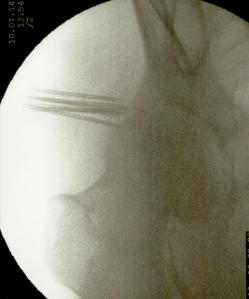

La artroplastia total de cadera para los casos de coxartrosis severa es el tratamiento de elección de la gran mayoría de cirujanos ortopédicos. Sin embargo cuando el paciente es menor de 50 años suele diferirse la intervención debido al tiempo de sobrevida del material protésico. También lo es en pacientes con deterioro del estado general debido a la avanzada edad o a enfermedades concomitantes (cardiópatas, por ej.) En estos casos la colocación de microimplantes de oro periarticulares alrededor del cuadrante súpero externo de la articulación es, habida cuenta del resultado sintomático y funcional, el tratamiento más indicado. La fácil colocación mediante control radioscópico y la rapidez de la recuperación (inmediata) hacen que este procedimiento sea seguro y muy útil para la remisión del dolor y la rigidez. No necesita ingreso ya que es una cirugía ambulatoria, se efectúa con anestesia local, y el paciente sólo requiere reposo relativo en el día de la intervención. Los resultados mediatos son excelentes. La mejoría clínica aumenta con los meses debido a la difusión de las nanopartículas de oro, por lo que contrariamente a los tratamientos convencionales que disminuyen su efecto con el tiempo, los microimplantes de oro lo mejoran. En cuanto esta técnica se popularice se reducirá significativamente el número de artroplastias.

Más abajo se observarán unas imágenes de casos de implantes de oro en cadera